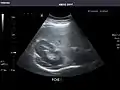

Renal ultrasonography

Ultrasound scan of a kidney (right side)

Ultrasonography of the kidneys is essential in the diagnosis and management of kidney-related diseases. The kidneys are easily examined, and most pathological changes in the kidneys are distinguishable with ultrasound.[7]